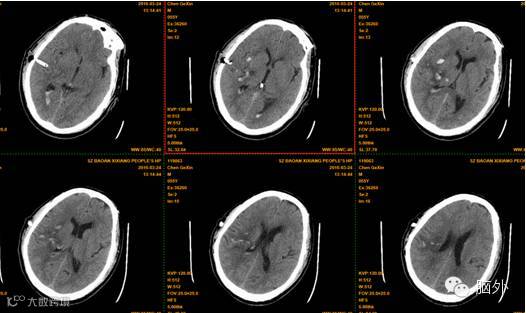

术后复查头颅CT提示脑内血肿几乎完全清除